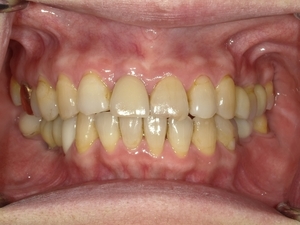

ガタガタとした歯並びや八重歯(叢生)CASE75